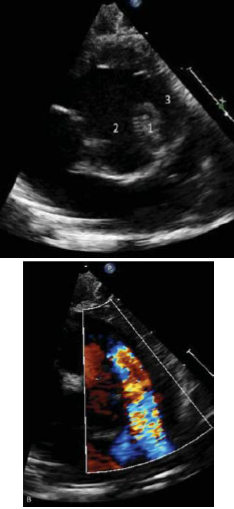

Sobre a patologia ilustrada na seguinte figura, é correto afirmar que